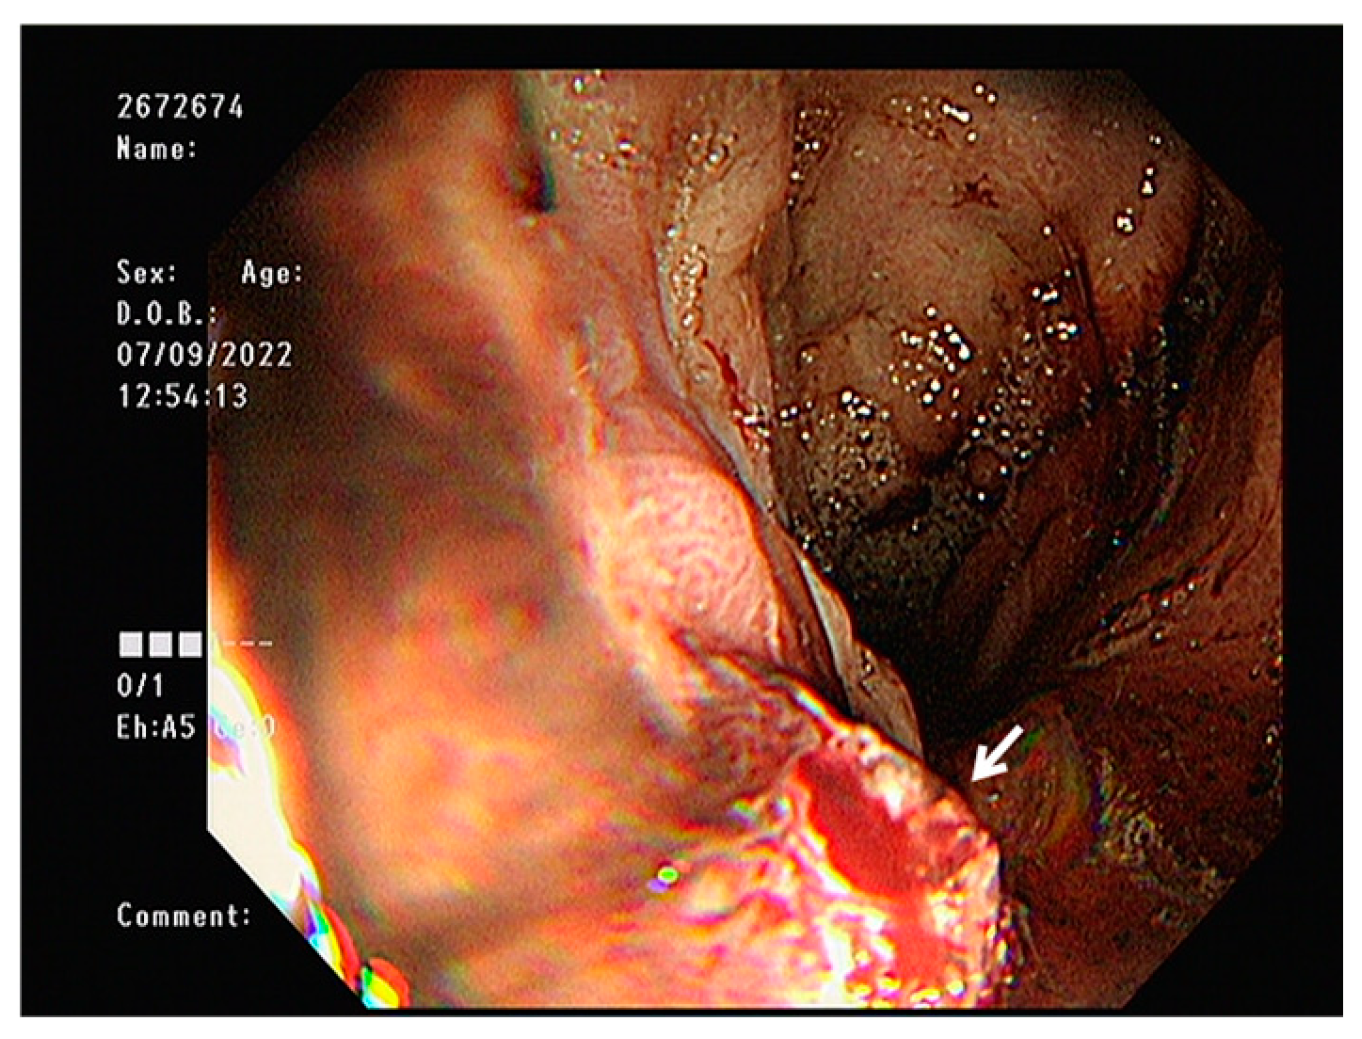

2. Case Presentation